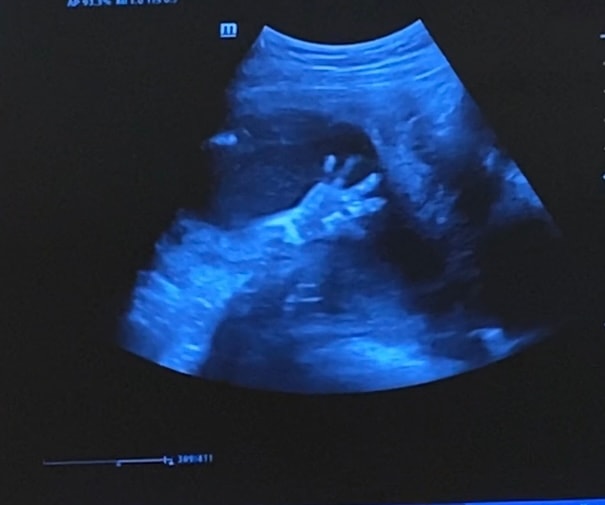

Как незаметно пролетело время , вот уже через пару дней середина беременности и пройденный второй скрининг , с малышом все отлично , весит 310 грамм , наш маленький богатырь 🙈отклонений никаких нет развиваемся по сроку ) Машем вам ручкой 😍